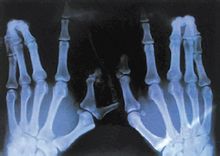

維生素D缺乏會導致少兒佝僂病和成年人的軟骨病。佝僂病多發於嬰幼兒,主要表現為神經精神症狀和骨骼的變化。神經精神症狀上表現為多汗、夜驚、易激惹。骨骼的變化隨年齡、生長速率及維生素D缺乏的程度等因素有關。可出現盧骨軟化、肋骨串珠等。骨軟化症多發生於成人,多見於妊娠多產的婦女及體弱多病的老人。最常見的症狀是骨痛、肌無力和骨壓痛。